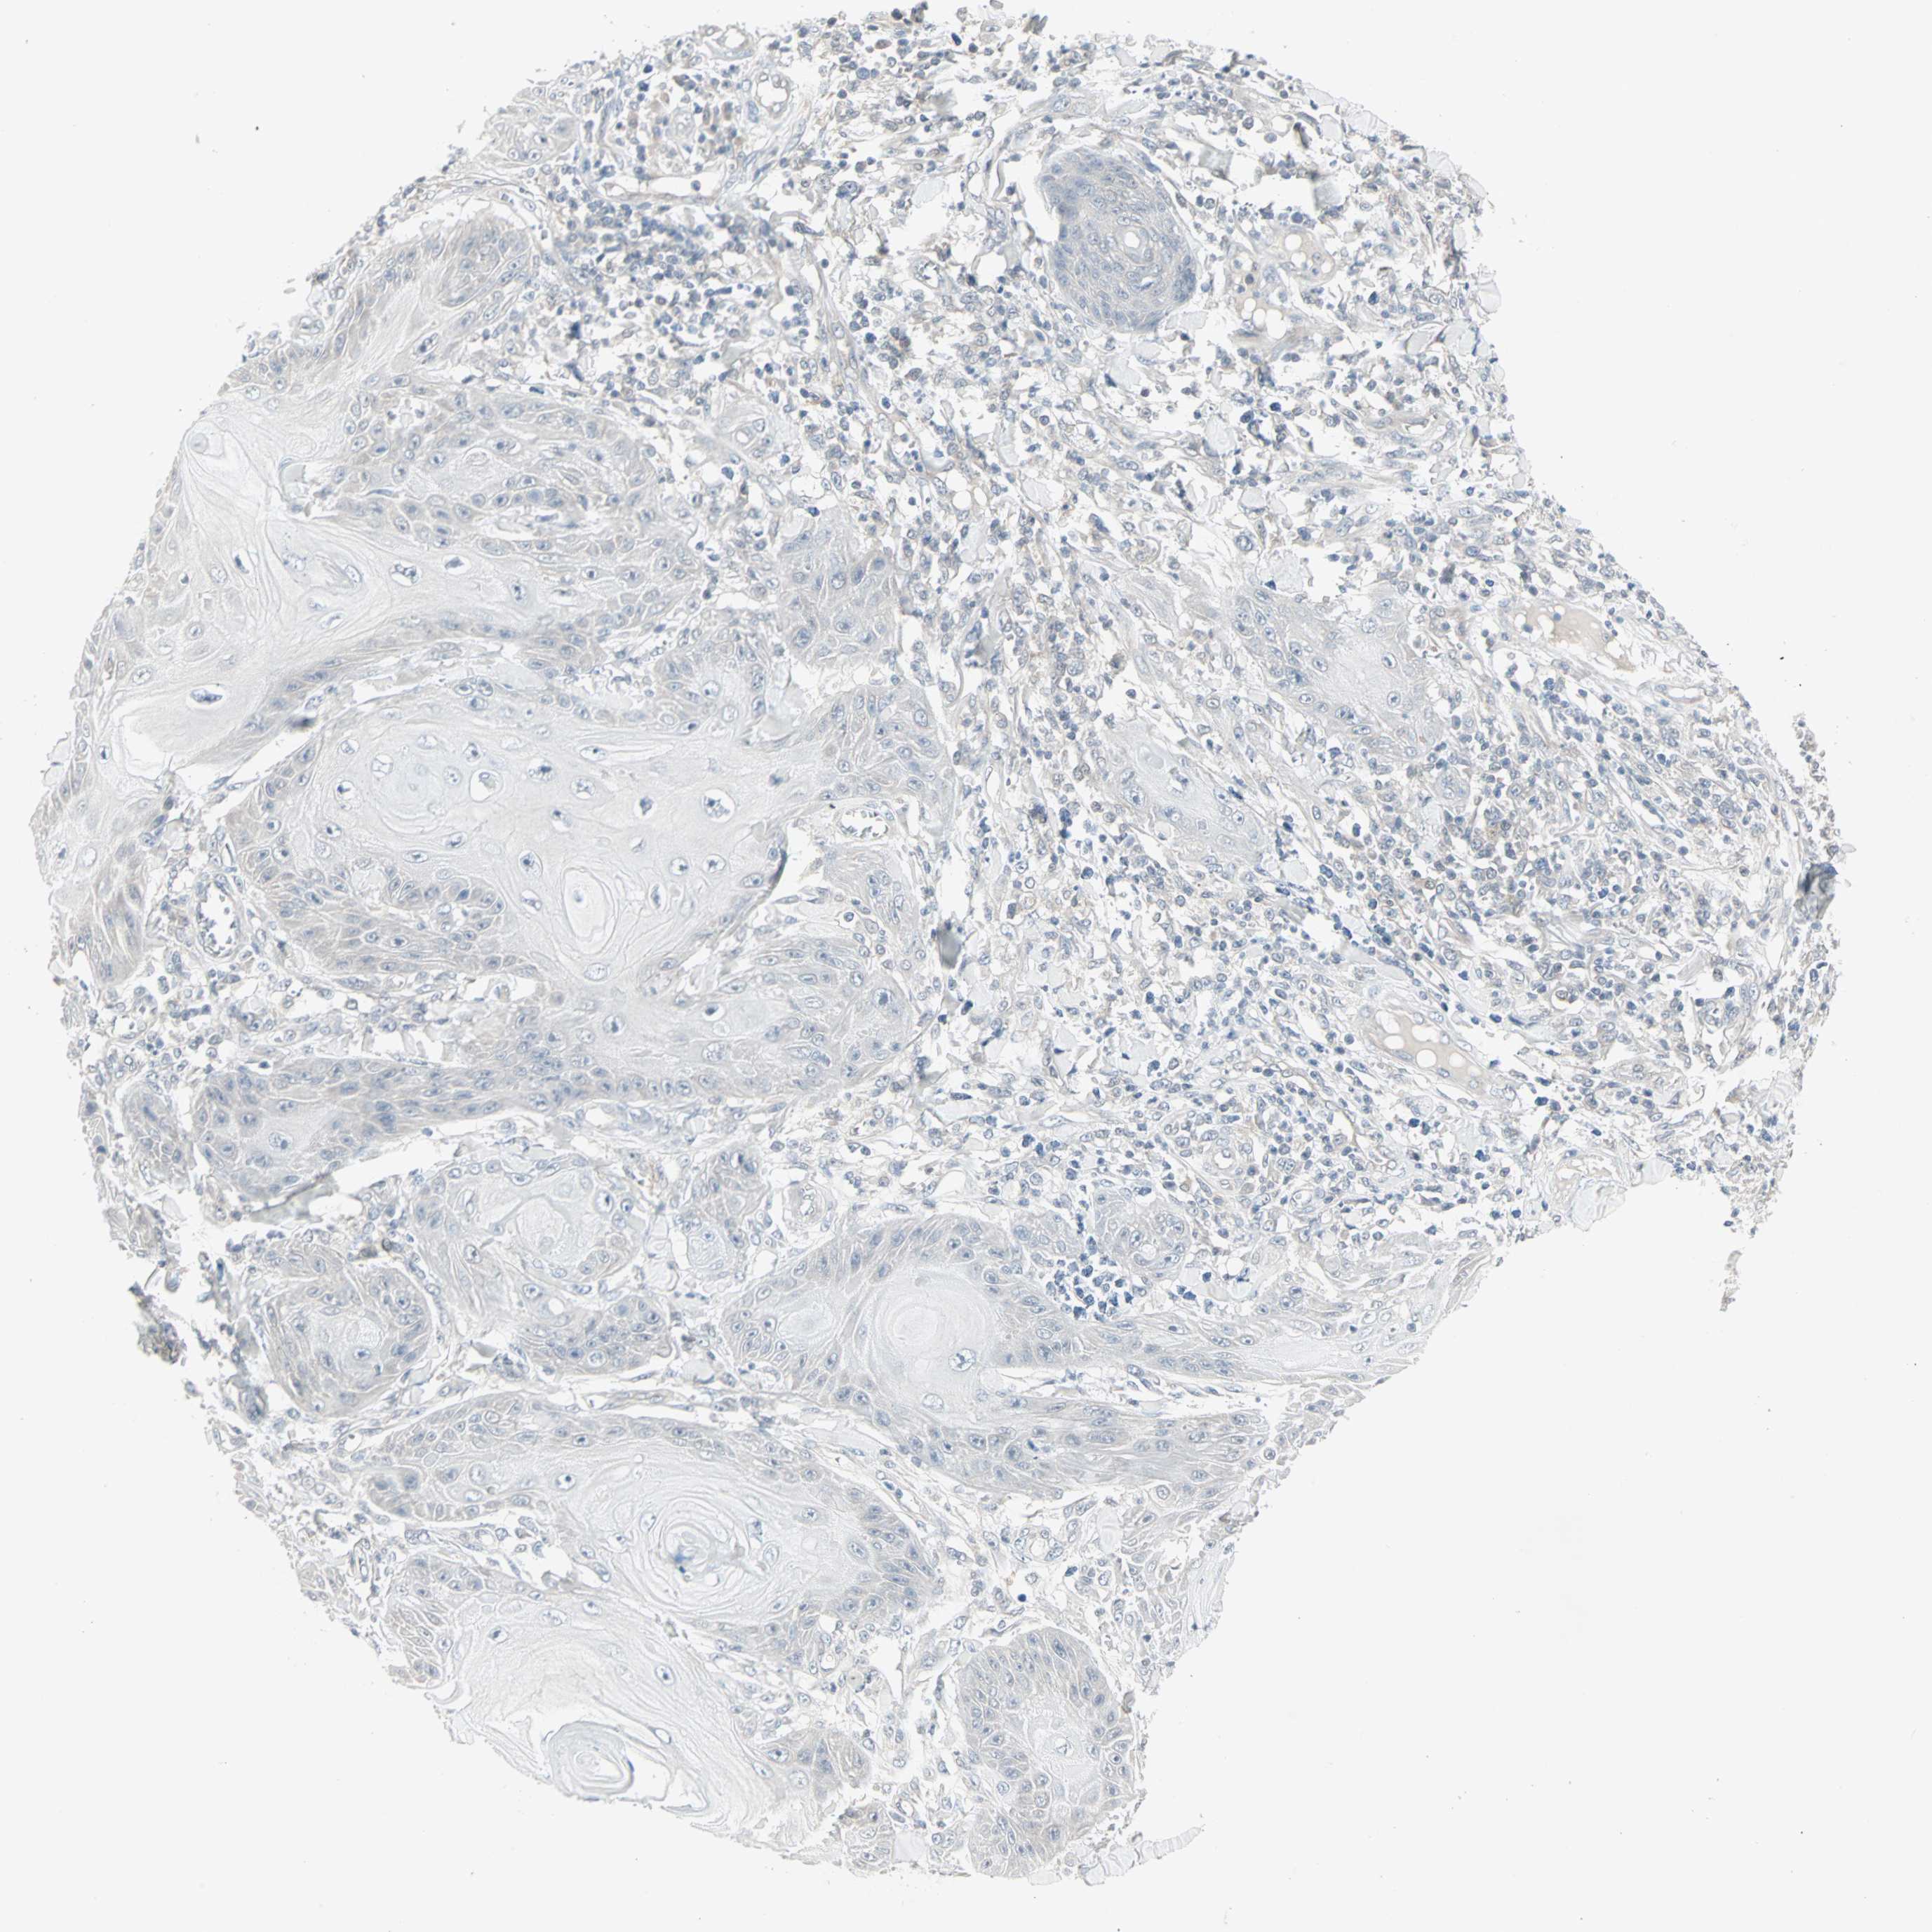

CANCER SKIN CANCER Show tissue menu

Basal cell and squamous cell cancer

SKIN CANCER - Protein expressioni

A mouse-over function shows sample information and annotation data. Click on an image to view it in a full screen mode. Samples can be filtered based on level of antibody staining by selecting one or several of the following categories: high, medium, low and not detected. The assay and annotation is described here.

Each image is clickable and will lead to virtual microscopy that enables deeper exploration of all samples and also displays staining intensity scores, fraction scores and subcellular localization as well as patient and tissue information for each sample.

Squamous cell carcinoma, NOS

Squamous cell carcinoma, metastatic, NOS

Basal cell carcinoma

Papilloma, NOS